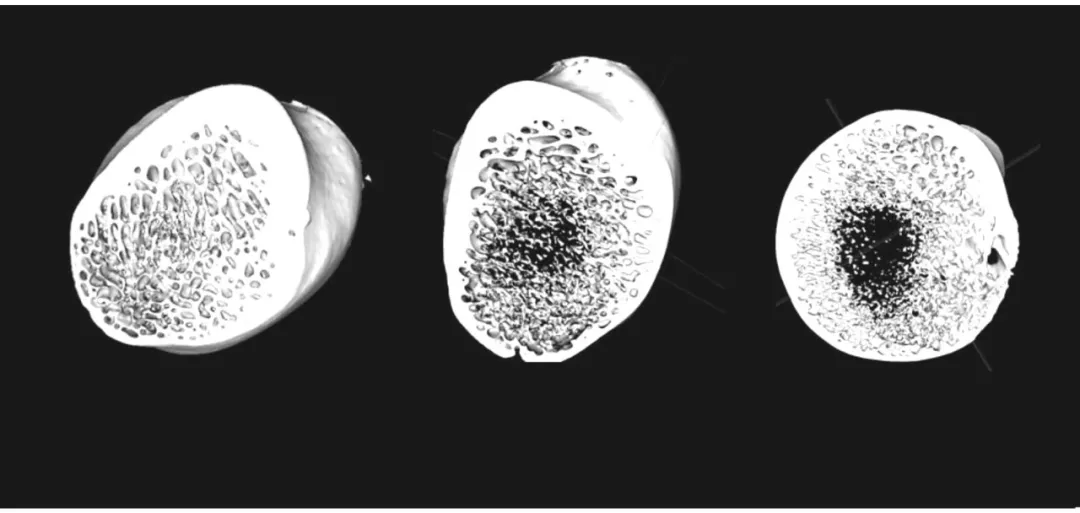

假手术组(左)与去势 4 个月组(中) 及去势 12 个月 组(右) 腰椎松质骨的三维重建图像。图片显示,去势 12 个月组的骨小梁较其他两组明显稀疏,孔隙率增加,水平方向骨小梁减少,局部有较大的骨小梁空隙形成。图片源于文献【1】。

假手术组(左)与去势 4 个月组(中)及去势 12 个月 组(右)股骨颈处松质骨的三维重建图像。图片显示,去势 12 个月后,股骨颈处松质骨有空腔形成,骨小梁明显变细,皮质骨壁变薄。图片源于文献【1】。